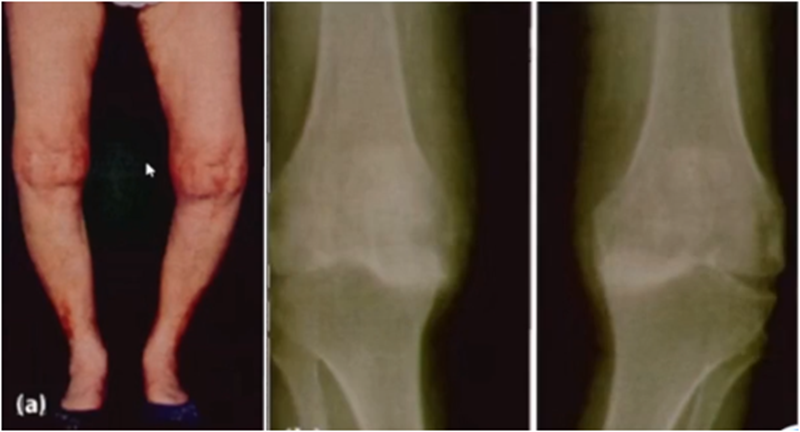

前内侧骨关节炎(AMOA)是人类特有的关节炎,关节压力在前内侧集中,是人类直立行走的代价。AMOA是临床中最常见的膝骨关节炎,占85%以上,通常多由磨损引起,AMOA是单髁置换(UKA)适应证选择的基石。

从影像学来讲,膝关节的磨损具有阶段性,是从轻到重发展的过程。影像学结合病史、体格检查是判断单髁置换适应证最有效的方法。

牛津单髁影像学判断的标准为通过负重正位片来判断内侧间室关节软骨的磨损程度。内侧间室关节间隙变窄,股骨内侧髁与内侧胫骨平台成“骨磨骨”状态,说明内侧间室软骨磨损丢失。如果没有在正位片观察到“骨磨骨”,则需要通过内翻应力位片或rosenberg位检查,找到骨磨骨的证据。如果以上均没有显示骨磨骨,需考虑关节镜检查,只有在达到“骨磨骨”的情况下才考虑行UKA。

AMOA查体与X线特点,站立位屈曲内翻

AMOA的X线正位的表现